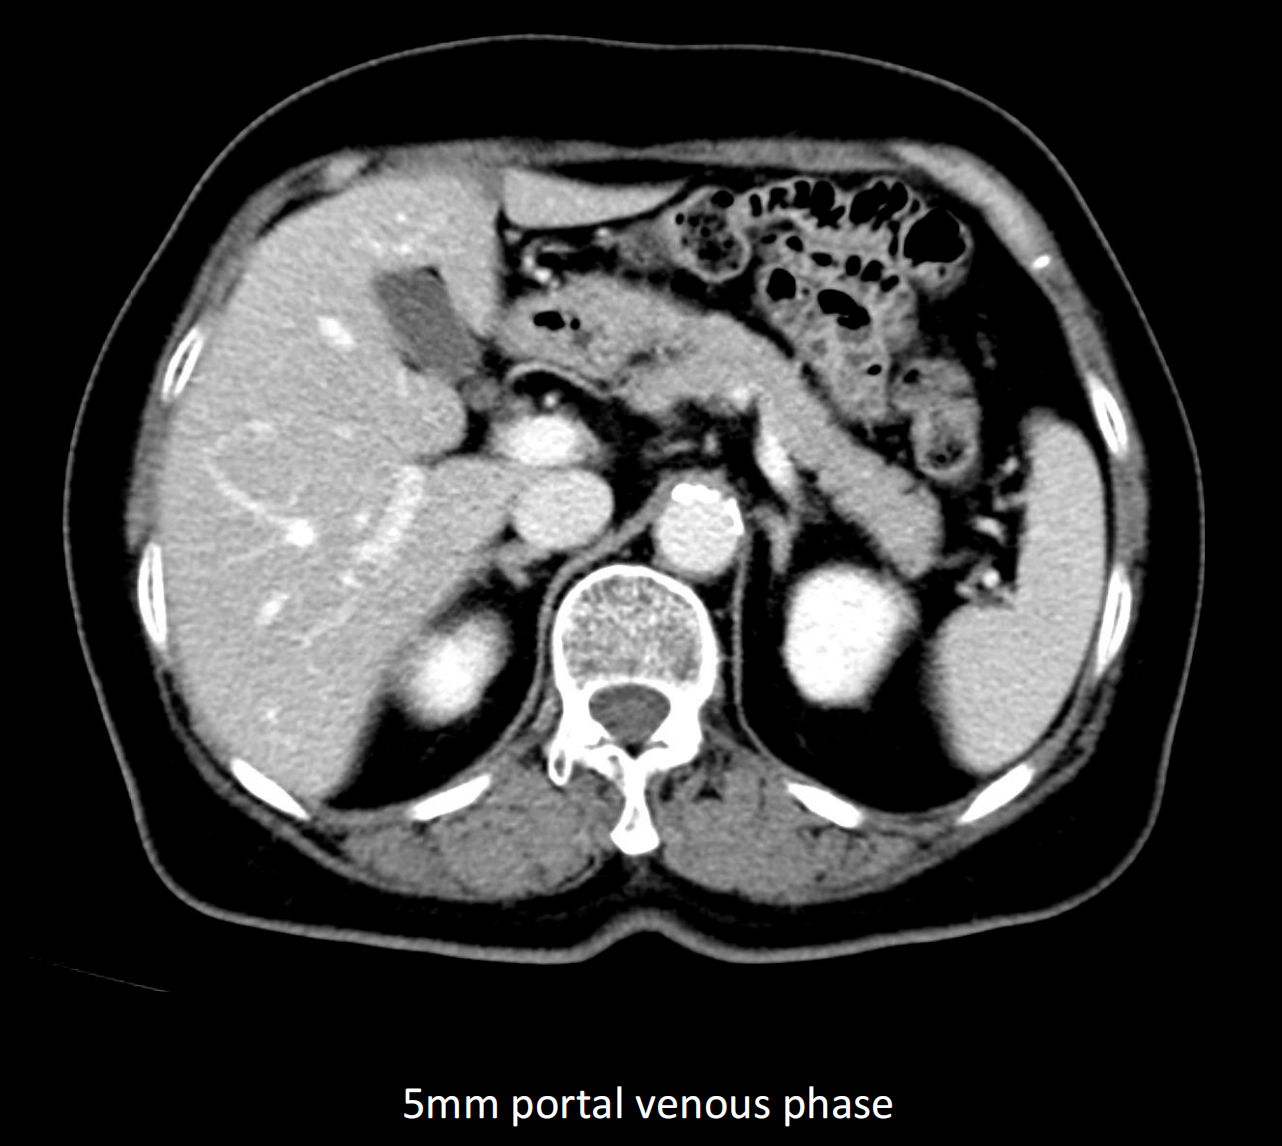

- Giải pháp chẩn đoán hình ảnh mô mềm tiên tiến cho khảo sát ổ bụng

- Tối ưu chất lượng hình ảnh chẩn đoán và giảm phơi nhiễm bức xạ

- Hỗ trợ đánh giá an toàn cho bệnh nhân

- Đảm bảo chất lượng hình ảnh chẩn đoán cao